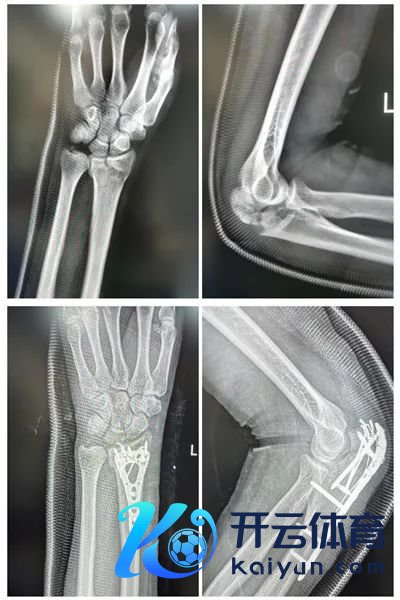

术前、术后X光

旧年,一场出乎有时的有时让何先生的生涯堕入了窘境。他从高处失慎摔落,导致一侧上肢尺骨鹰嘴、桡骨远端破碎性的骨折,及不同程度的胸腰椎、骨盆骨折,这一重创无疑是对他身心的宏大训诲。然则,在佛山市中病院三水病院的经心调节与门诊系统康复介入的匡助下,何先生不仅得手克服了躯壳上的挑战,更在精神上展现了惊东说念主的坚忍与意识。

事故发生后,何先生被飞速送往病院,并得手汲取了由骨六科郑泓副主任中医师主刀的手术调节。常言说念“三离婚术,七分康复”,术后康复的早期介入关于骨折愈合和功能收复相等伏击。